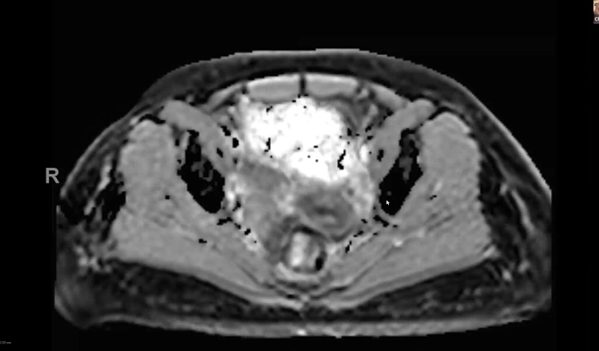

endometrial adenocarcinoma, para-aortic nodes, PET CT, diabetes, charcot arthropathy, groin nodes, pelvis, negative cervical margins, cisplatin, small bowel, Harkenrider, contouring, MRI, tumor, vaginal bleeding, relapse, persistence, cylinder, dose distribution, dosimetry, brachytherapy, fractio...

squamous cell carcinoma, dysplasia, PET, SIB, brachytherapy, endocervical, MRI, nodal location, inguinofemoral, right external iliac, CTV, deescalation, dosimetry, sigmoid, hysterectomy, concurrent chemoradiation, stenotic cervix, abdominal infection, external planning, avoid structure, antibioti...

chemotherapy, radiation therapy, sandwich regimen, brachytherapy, well differentiated endometrioid adenocarcinoma, neoadjuvant chemotherapy, small bowel, dilation, dosimetry, gross disease dose, MRI, cirrhosis, external beam radiation, Rotte Y applicator, CT scan, dual tandem, 3-D printing, endom...